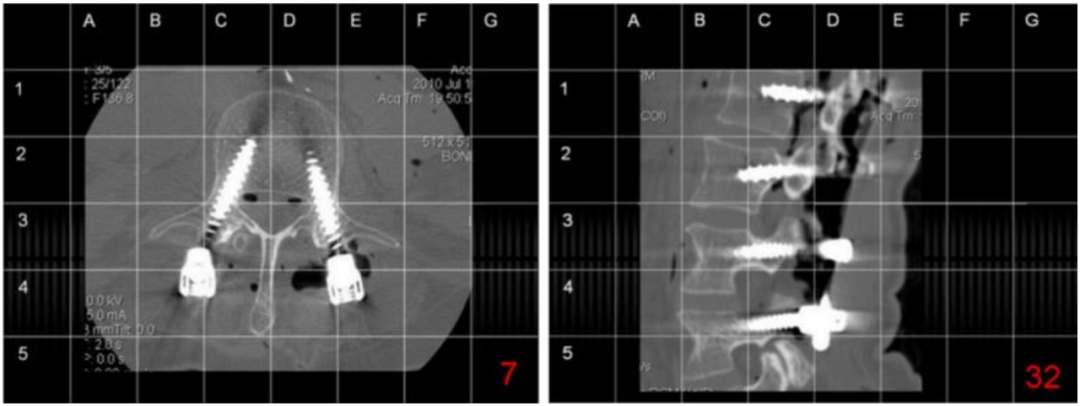

研究表明,醫(yī)用鈷鉻鉬材料的核磁共振成像偽影小,是穩(wěn)定脊柱內(nèi)固定系統(tǒng)的優(yōu)良材料之一。

腰椎鈦和鈦鈷植入系統(tǒng)的整體圖像清晰度對(duì)比,結(jié)果令人滿意。